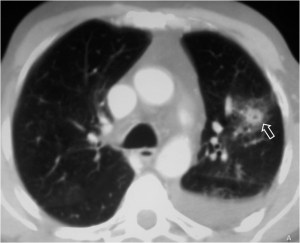

Otro ejemplo del signo del halo (flecha).

Este magnífico ejemplo de signo del halo corresponde a un paciente con metástasis de angiosarcoma. Mi agradecimiento a la sección de radiología tórax de mi hospital (Dra. Maribel Padín y Dra. M. Carmen Aguilar) y a Kiko Padilla, que hizo una lectura perfecta del caso.